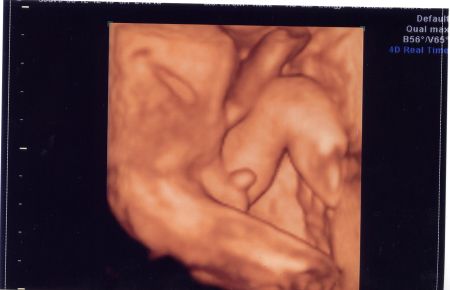

Sziasztok lányok!

Szerintetek most már bizti, hogy ki lakik a pocimban? :D

655 g és minden rendben. De állandóan takarta a kis arcát igy teljes képet nem sikerült róla csinálni. Kép Kép

Édes kis fütyikés!! Gratulálok!

Nagyon jók a képek!

Gyönyörű tesóbaba, talán már megnyugodhattok, hogy nem változtat nemet, és nem nézték el :lol: :lol: :lol:

gyöngyi, nagyon tetszik, hogy ennyire egyértelműen látszik, ki lakik odabent :D